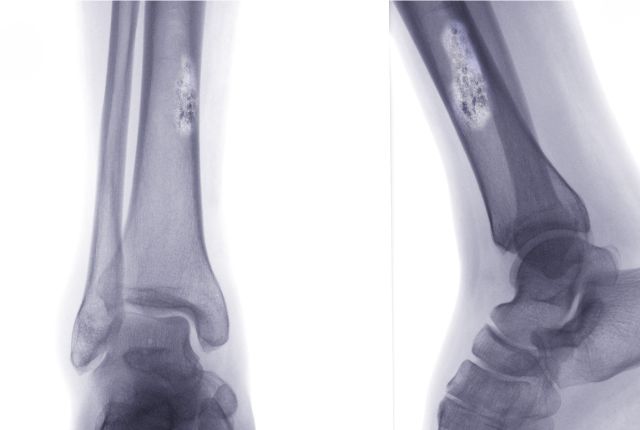

Radiographie

La radiographie permet de déceler des anomalies au niveau des os, une excroissance, voire un trou. Il est difficile néanmoins de conclure avec cet examen si la tumeur décelée est cancéreuse ou non. Dans certains cas, il permet néanmoins d'écarter le diagnostic de cancer comme dans la maladie de Paget.

L' ostéosarcome touche généralement les os du tibia et du fémur (os longs), mais aussi le genou. Cette tumeur rare et agressive touche souvent les jeunes hommes.